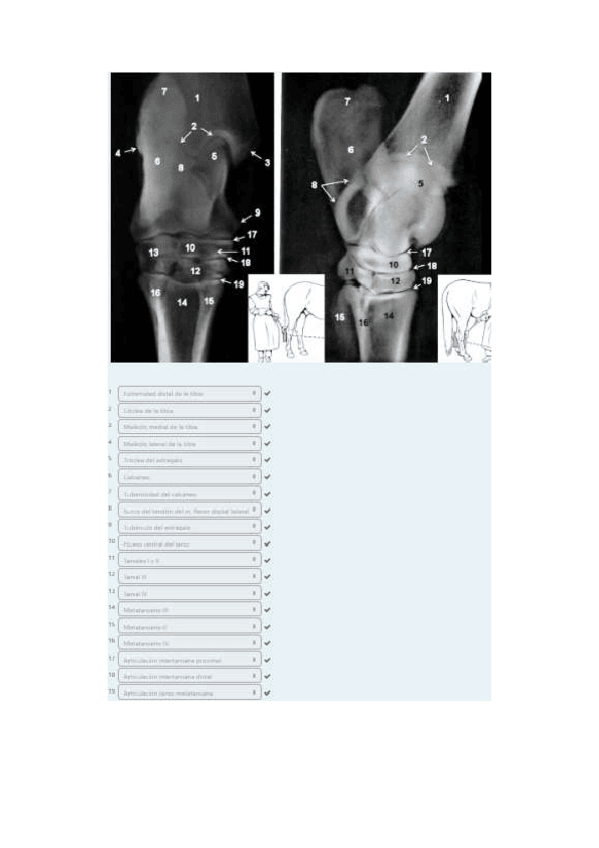

He publicado nuevos apuntes de 1º EMBRIOLOGÍA Y ANATOMÍA I: Radiografías práctica 6.pdf

8 páginas

He publicado nuevos apuntes de 1º EMBRIOLOGÍA Y ANATOMÍA I: Radiografías práctica 3.pdf

5 páginas

He publicado nuevos apuntes de 1º EMBRIOLOGÍA Y ANATOMÍA I: Radiografías práctica 5.pdf

10 páginas

He publicado nuevos apuntes de 1º EMBRIOLOGÍA Y ANATOMÍA I: Radiografías práctica 7.pdf

13 páginas

He publicado nuevos apuntes de 1º EMBRIOLOGÍA Y ANATOMÍA I: Radiografías práctica 8.pdf

12 páginas

He publicado nuevos apuntes de 1º EMBRIOLOGÍA Y ANATOMÍA I: Radiografías práctica 4.pdf

9 páginas